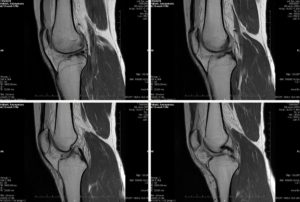

МРТ– практически единственный способ установить подобный диагноз, неважно, поврежден коленный или локтевой сустав, правый или левый сегмент. Быстрый способ начать восстановление – отреагировать немедленно и делать все, что советует врач, а не тянуть время, в особенности, если это случилось повторно.